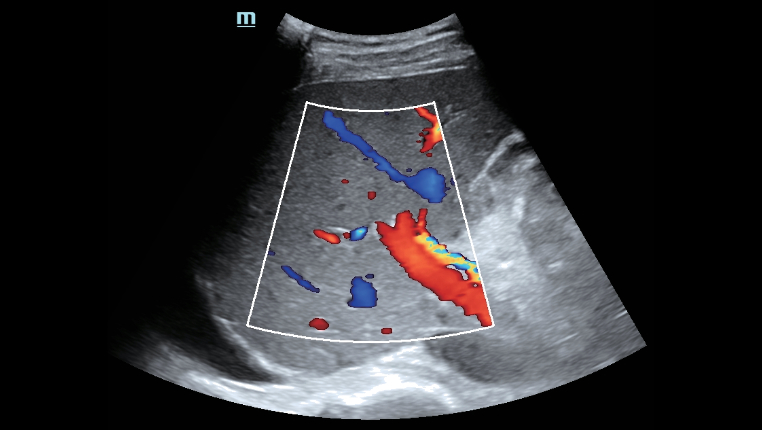

┬и Exzellentes Ultraschallbild und ebensolche Ultraschallfunktion erm?glichen umfassende Bewertung von Lebermorphologie und H?modynamik.

┬и Exzellentes Ultraschallbild und ebensolche Ultraschallfunktion erm?glichen umfassende Bewertung von Lebermorphologie und H?modynamik.